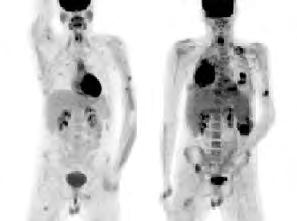

2.6.4 Radionuklidové metody (Daniela Chroustová) 35